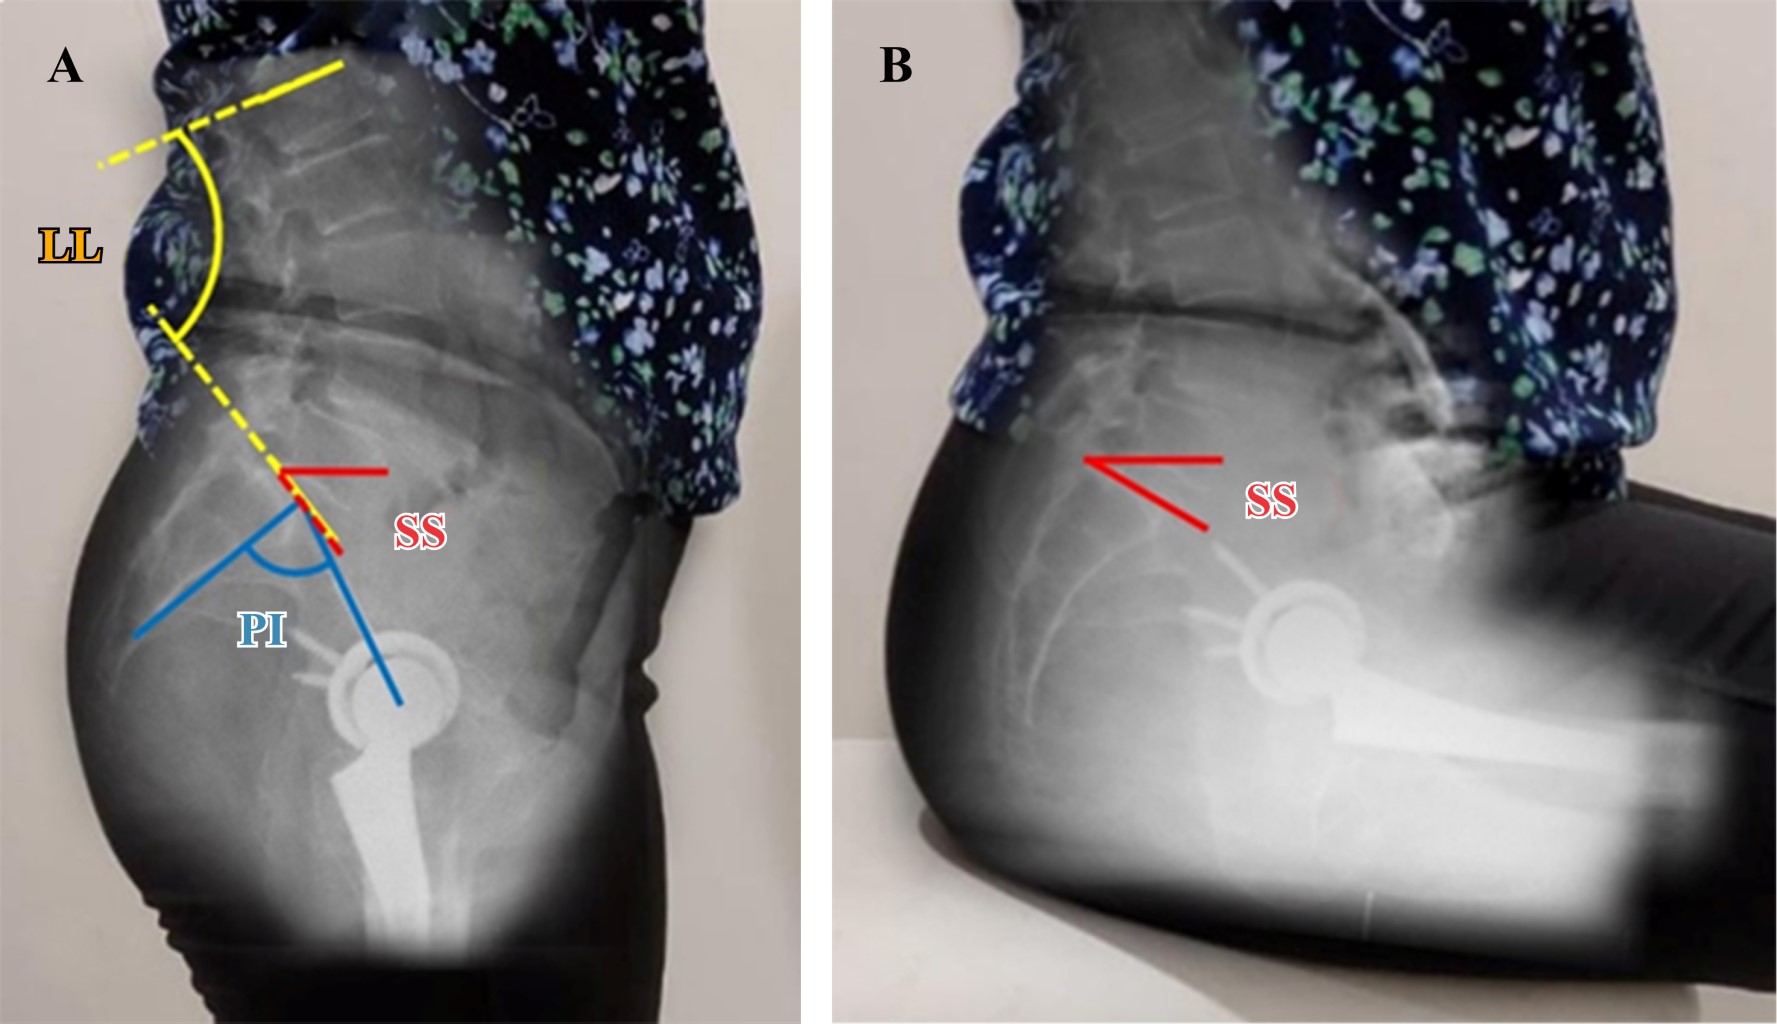

Introduction: the analysis of spinopelvic imbalance in patients undergoing total hip arthroplasty has gained significance in recent years, being recognized as a risk factor for instability. Few reports exist regarding the prevalence of spinopelvic alterations in Latin American literature. The aim of this study is to determine the frequency of spinopelvic imbalance in our patients and to associate them with functional outcomes. Material and methods: 29 patients who underwent total hip arthroplasty using a lateral approach (32 arthroplasties) were included. All patients completed clinical outcome questionnaires preoperatively. Twelve months after surgery, they underwent anteroposterior pelvic and lateral pelvic X-rays, both standing and sitting, and clinical outcome questionnaires were completed. The radiographic parameters examined were: pelvic incidence, lumbar lordosis, sacral slope, anterior pelvic plane and pelvic femoral angle. Functional outcome was assessed with the Harris Hip Score and WOMAC scales. Patients were classified according to their spinopelvic alteration and statistical analysis was performed to identify significant differences between the groups and the correlation with functional outcomes. Results: there was a high frequency of spinopelvic balance alterations (46.8%); 6.2% (n = 2/32) presented isolated spinal stiffness (group 1B), 37.5% (n = 12/29) spinal deformity without spinal stiffness (group 2A) and 3.1% (n = 1/29) spinal deformity associated with stiffness (group 2B). We found no improvement in HHS and WOMAC scores in the groups with spinal stiffness (1B and 2B) (p = 0.98 y 0.15). There is association between spinal stiffness (ΔSS < 10°) and poor functional outcomes (p = 0.02). Conclusions: the frequency of spinopelvic balance alterations was high. While there was no observed rise in prosthetic dislocations, the existence of spinal stiffness, defined by a ΔSS of less than 10°, was associated to poor outcomes on functional scales.

Figure 2